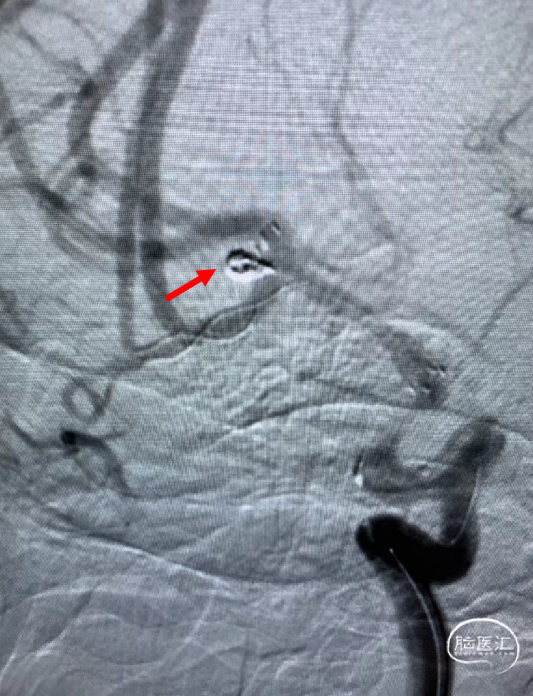

术后造影显示动脉瘤致密栓塞,各分支血管血流通畅。

术后双容积成像显示支架头端完全覆盖动脉瘤瘤颈,并且与Solitaire支架形成“Kissing”,“T型”形成。